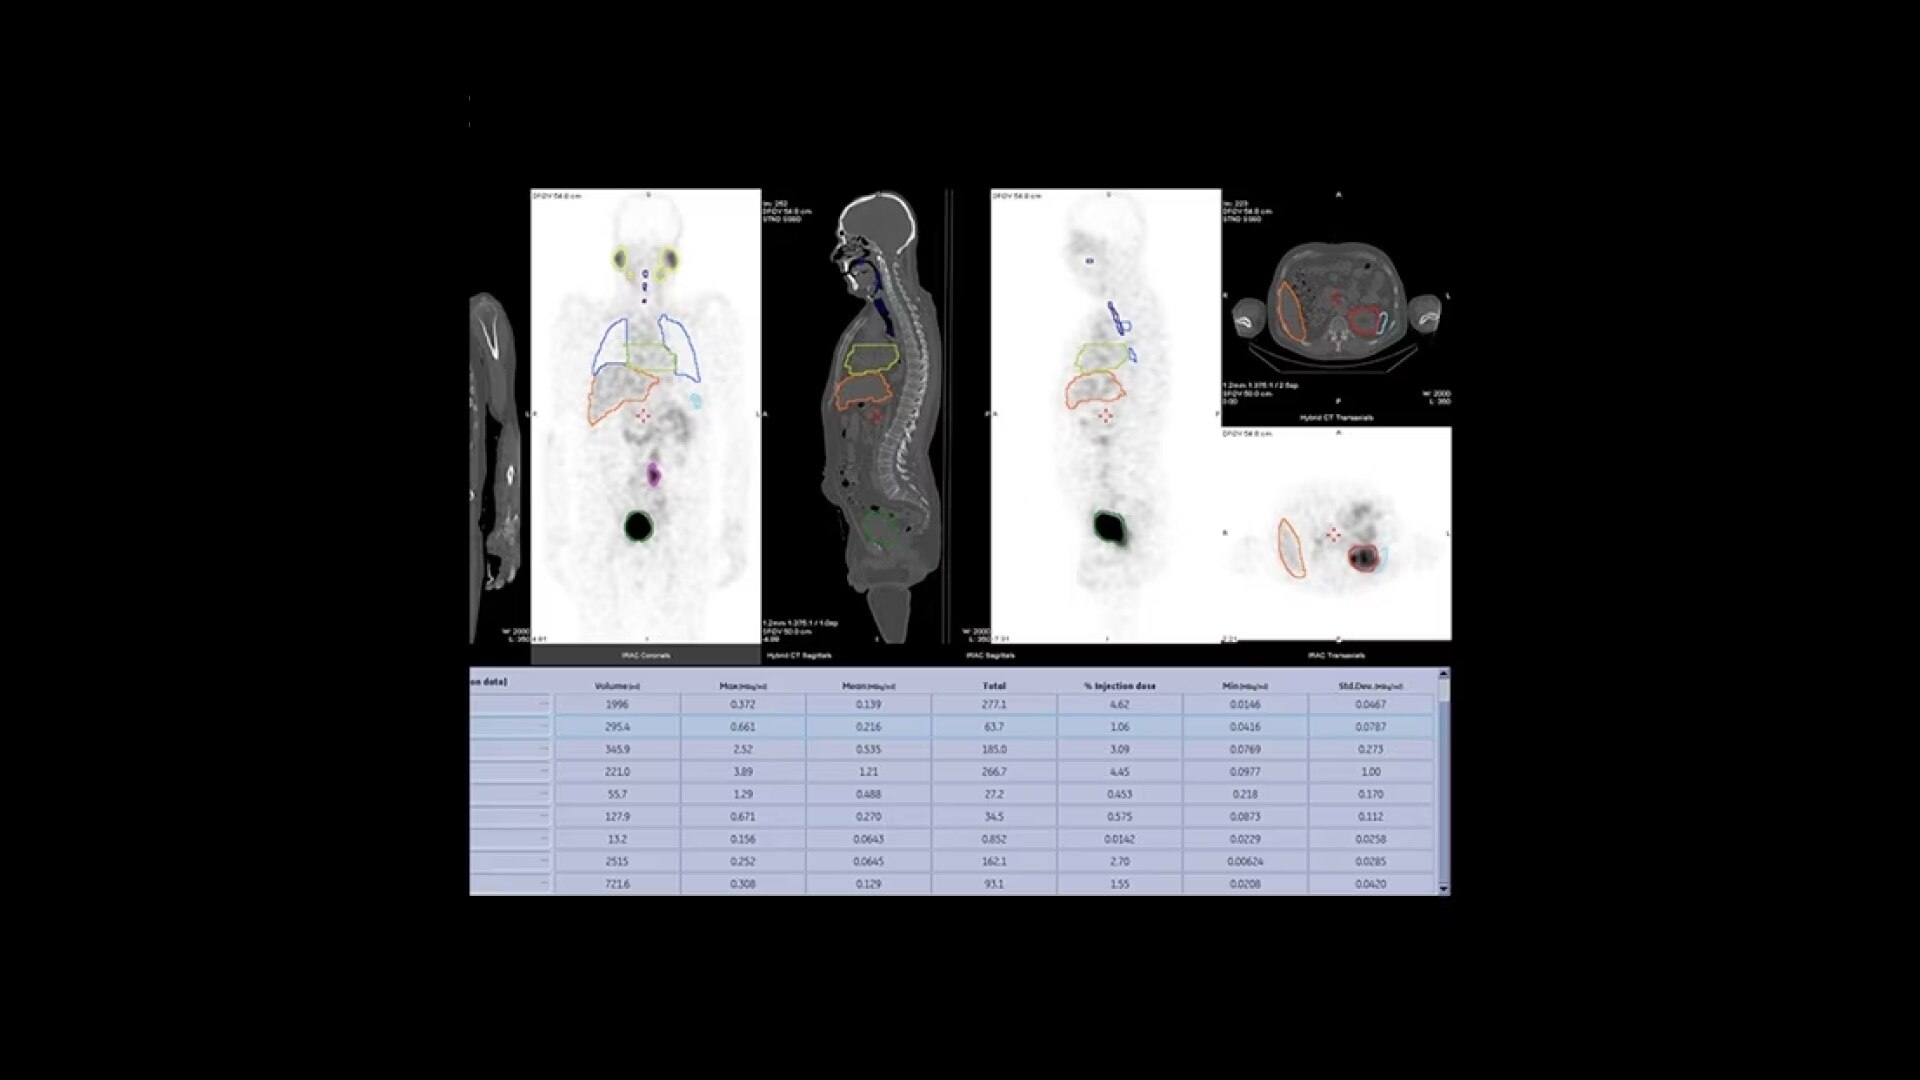

Switch to an all-digital workflow with SmartConsole

SmartConsole is an all-new productivity hub for hybrid imaging. By automating SPECT/CT reconstruction, SmartConsole simplifies the workflow for complex hybrid and quantitative protocols and allows technologists to review results directly at the scanner console. It also allows physicians to review scans remotely from their own mobile devices. They can modify processing settings and initiate study processing anytime, anywhere across a LAN or a WAN*.

SmartConsole enables a noticeable improvement in productivity. Now, a physician can provide their input remotely and digitally. For example, physicians can review a whole-body bone scan directly on their tablet or other mobile device and define the scan range limits they need from wherever they are. The time saved with this switch to a digital workflow helps make it possible to complete exams in predictable time slots.

SmartConsole makes advanced procedures more accessible by transferring exams directly to the PACS or other pre-defined DICOM destinations with no operator intervention, even if SPECT/CT fusion is not supported, by exporting the studies in DICOM PET format.

You can generate and send an additional dataset in PET DICOM format to enable quantitative SPECT results and SPECT SUV (Standard Uptake Value) on any PET DICOM compliant workstation or PACS. As a result, referring physicians can review and evaluate your SPECT/CT exams with the same quality of information they have come to expect from your PET/CT, as adjunct information to the original SPECT/CT images.